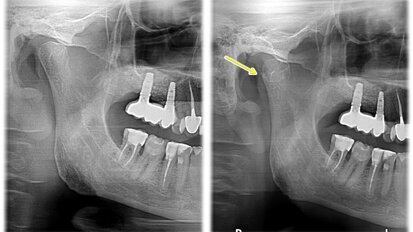

Leczenie endodontyczne autogennego przeszczepu zęba z zastosowaniem lasera Er,Cr:YSGG

Chociaż dotychczasowe publikacje przedstawiają różne techniki chirurgiczne, żadna z nich nie opisywała alternatywnych strategii leczenia ...

zapisz